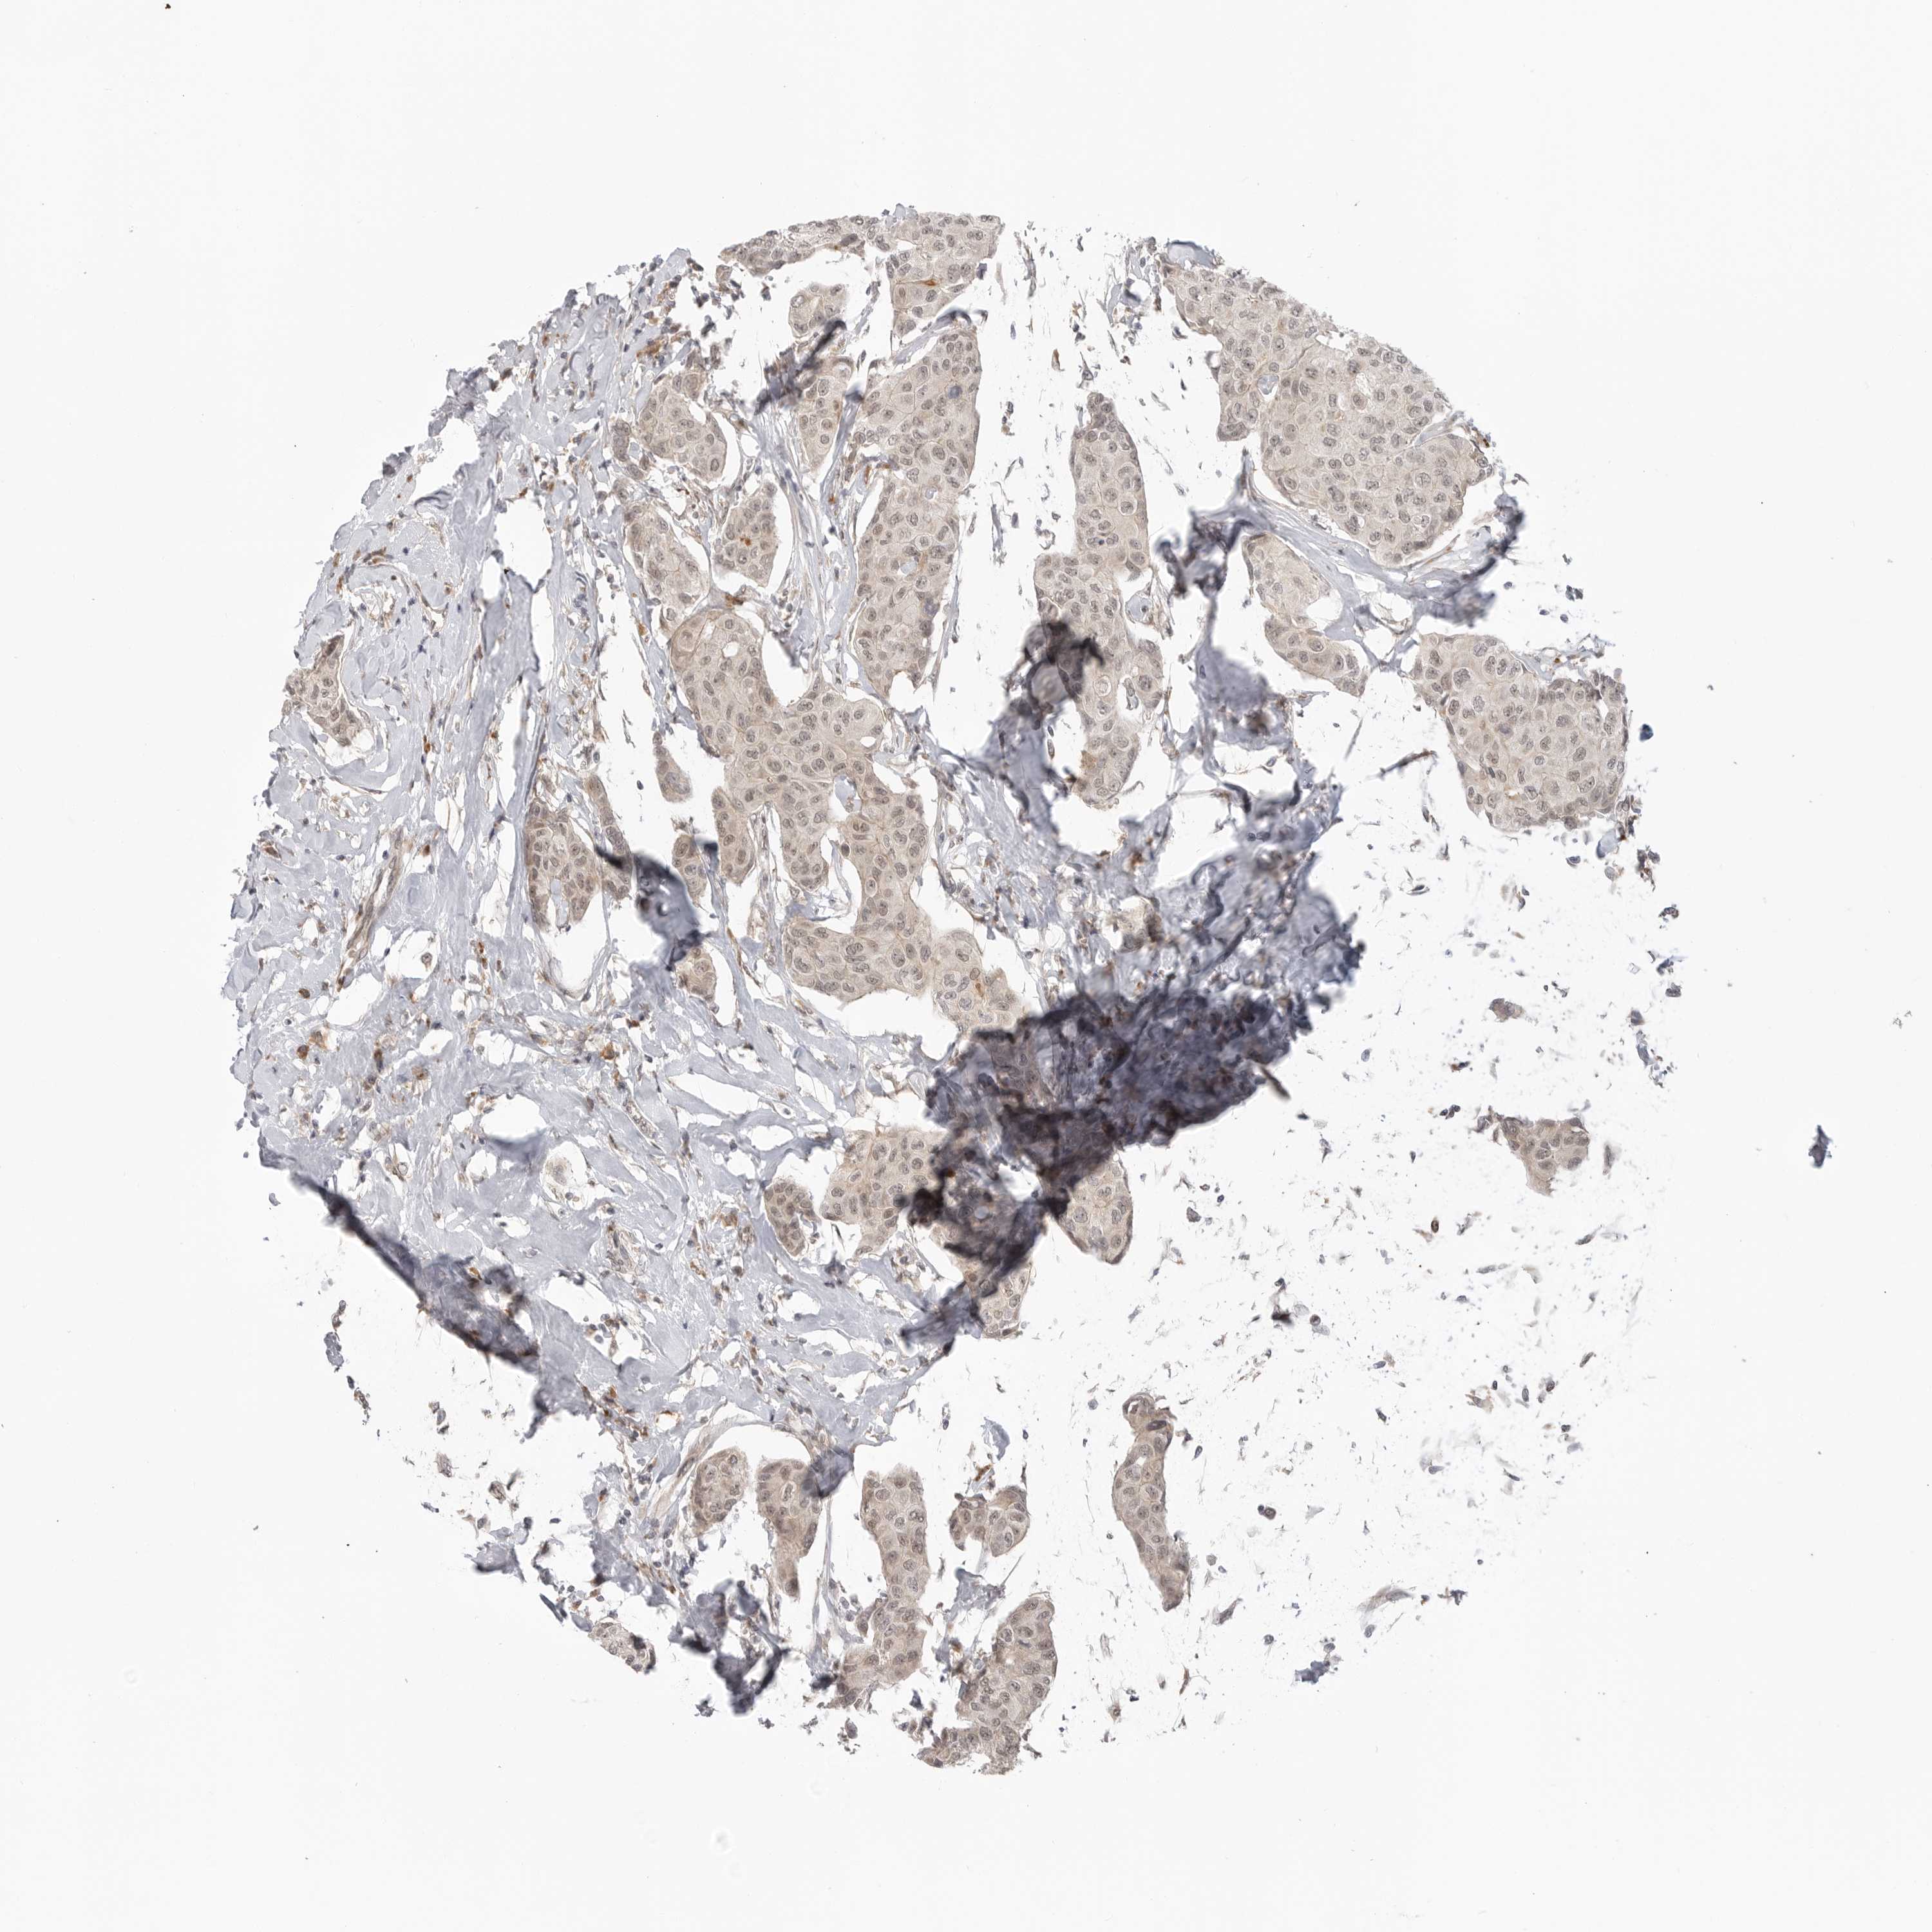

CANCER BREAST CANCER Show tissue menu

BRCA TCGA BRCA VALIDATION PROTEIN EXPRESSION